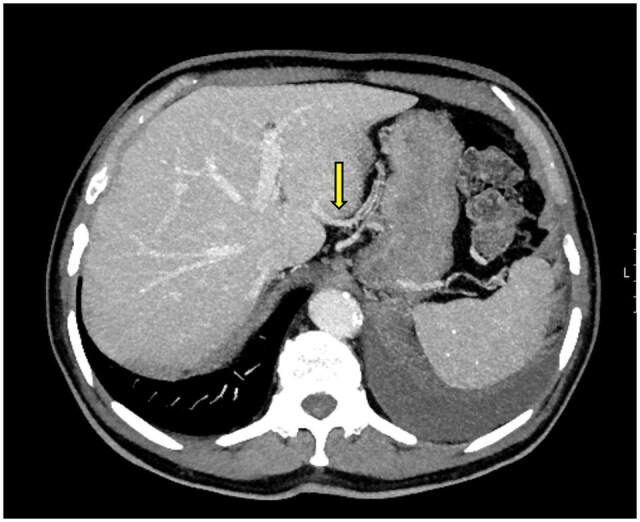

第三流是指肝脏在双重血供之外,从第三个来源增加的血供。异常的左右胃静脉、Sappey静脉和Barlow静脉以及旁静脉系统被认为是第三流最重要的例子。临床上,第三流很重要,因为它与肝脏假性脓肿有关,并在肝胆和胃手术中增加手术并发症的风险。我们的病例系列包括8例异常胃左静脉(ALGV)和1例Sappey静脉。除了介绍ALGV和供应静脉的例子外,我们还重点介绍了在肝移植供体和胃癌病例中观察到的肝脏缺血性并发症。我们的目的是强调与algv相关的手术风险和术前影像学评估血管变异的重要性。

Third inflow refers to the additional blood supply to the liver from a third source, apart from its dual blood supply. Aberrant right and left gastric veins, Sappey and Barlow veins, and the parabiliary venous system are considered the most significant examples of third inflow. Clinically, the third inflow is important due to its association with hepatic pseudolesions and its role in increasing surgical complication risks in hepatobiliary and gastric procedures. Our case series includes 8 cases of aberrant left gastric vein (ALGV) and 1 case of a Sappey vein. In addition to presenting examples of ALGV and Suppey vein, we also highlight ischemic complications of the liver observed in a liver transplant donor and a gastric cancer case. Our aim is to emphasize ALGV-related surgical risks and the importance of assessing vascular variations in preoperative imaging.